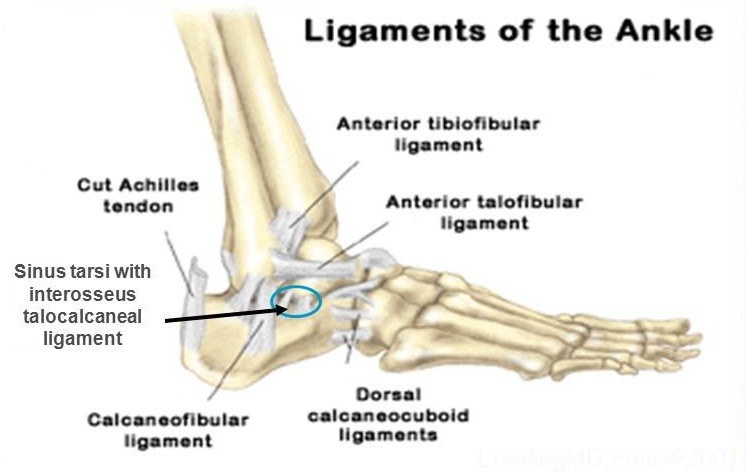

족근관(Tarsal canal)과 족근동(Sinus tarsi)은 후방 거골하관절과 전방의 거종주상관절(talocalcaneal navicular joint) 사이의 경계에 형성하고 있다. 족근관과 족근동은 후내측에서부터 전외측까지 이어져있다. 족근관은 재거돌기 후방 발의 내측방향으로 연장된다. 족근관은 족근동의 형성으로 넓어지는데, 원뿔 모양으로 가쪽으로 열려있다. 족근동에는 지방, 혈관, 골간인대, 경골신경의 가지들이 존재한다.

△ Sinus tarsi with interosseus talocalcaneal ligament